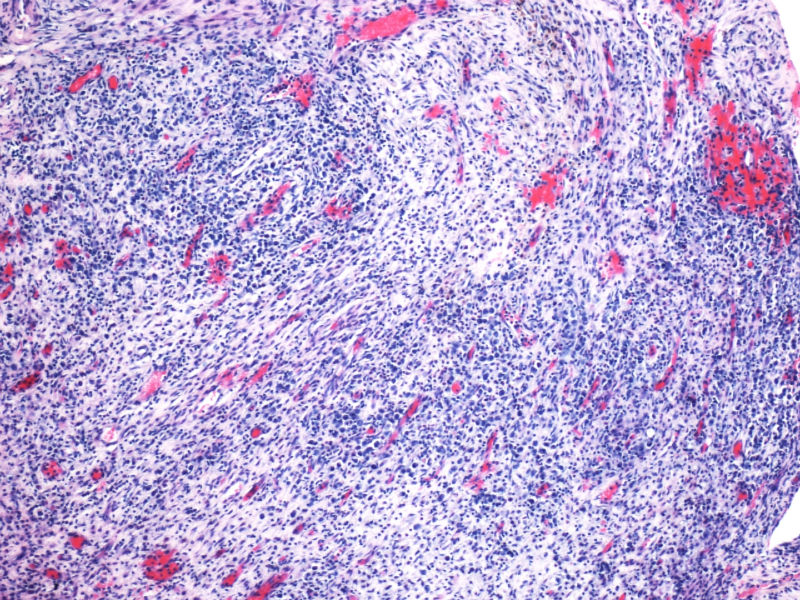

形态学hallmark 细胞显示不是很清晰,大的肿瘤细胞如果在ALCL和HL之间选择可能不容易,但HL的肿瘤细胞形态学特点的范围比较狭窄,而ALCL可能具有更广泛的形态学范围,细胞大小形态以及典型hallmark cell的多少有时很难确定。如果只看HE,觉得ALCL的可能会安全一点,当然我个人经验不足,可能理解得比较肤浅。

本例CD68的表达也许很重要,HL可以有严重的炎症背景,但背景细胞是否会出现如此明显CD68阳性细胞,还请各位老师教我;而ALCL CD68大概可以阳性。另外就是哪些细胞是肿瘤细胞的问题了,可能未必局限于CD30阳性的大细胞吧。